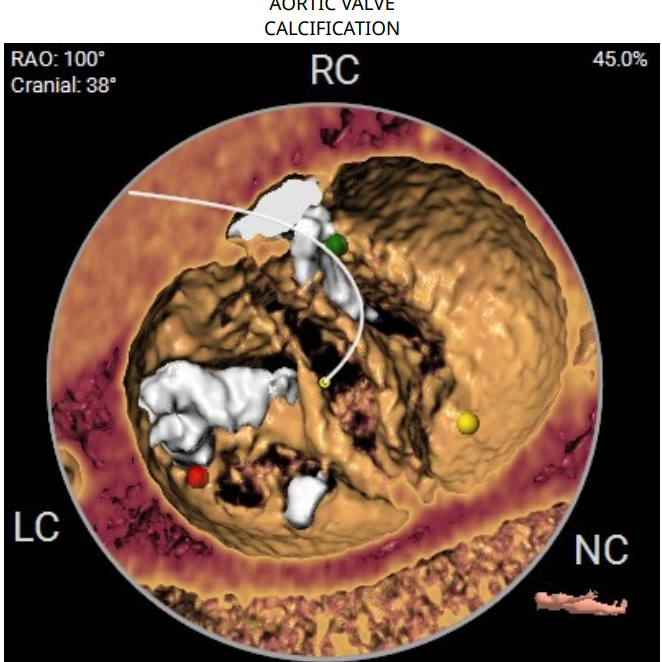

CT分析:

术前CT分析判断该心耳为反鸡翅型左心耳,选择偏下略偏前的位置进行房间隔穿刺。在工作体位造影后,可见左心耳内梳状肌发达,反鸡翅叶显影清晰,鞘管轴向佳。经DSA测量左心耳开口18mm深度17mm,结合TEE测量数据,综合考虑选用WATCHMAN24mm封堵器进行封堵。在展开封堵器时利用在体内借深度技巧,保证封堵器封堵位置合理。封堵器展开后经造影检查封堵器封堵效果理想,牵拉试验稳定。超声评估封堵器各角度无残余分流,位置理想,满足PASS原则,随即释放封堵器,一站式手术顺利结束。